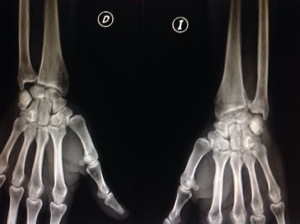

Vean seguidamente el ejemplo de un paciente que presentaba una lesión de Essex-Lopresti con conminución de la cabeza de radio, al que le fue practicada de urgencias una resección de la cabeza de radio. A los 2 meses presenta un acortamiento tal del radio que el paciente tenía una prono/supinación bloqueada a 0grados.